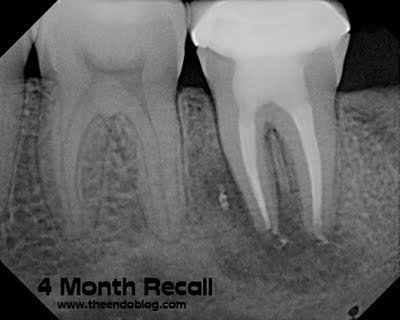

4 month initial healing seen.